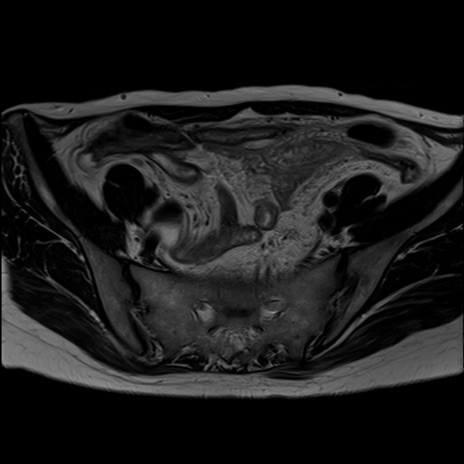

症例39 T2WI(横断像)

MRI(4日後)